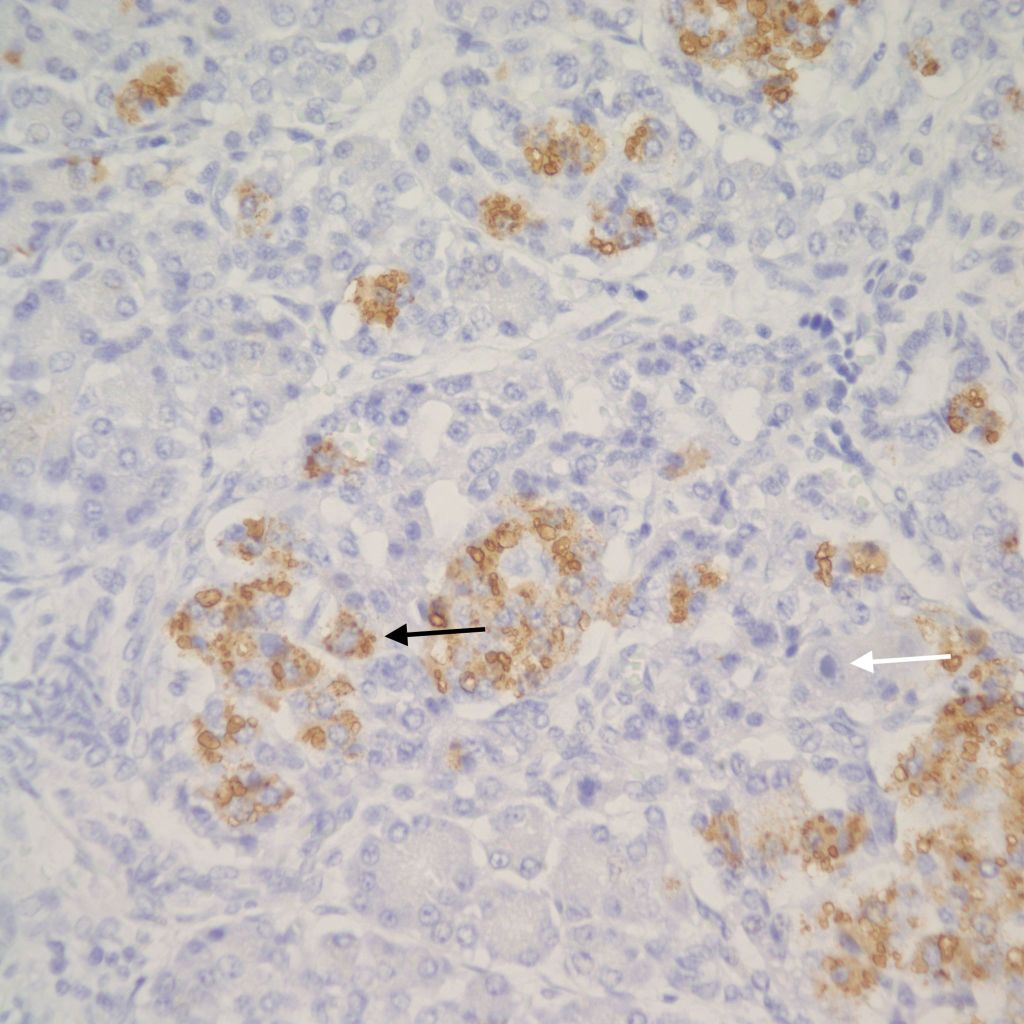

However, islet cell type and distribution in the pancreas is not homogenous throughout the organ and also changes with gestation. An increase in islet area may be difficult to determine without quantitative technique and comparison with matched controls for gestation and location within the pancreas. Beta cells that secrete insulin and amylin, normally make up greater than a majority of cells in an islet. Therefore, the percentage of beta cells in an islet is seldom helpful determining an overall hyperplasia of insulin secreting cells. A more reliable feature to identify evidence of increased islet response is cell hypertrophy. These hypertrophic cells are polyploid with clearly enlarged nuclei compared to surrounding cells (Fig 6).

The cytomegalic cells can be identified even with marked autolysis of the pancreas (fig 7).

The hypothesis is that both hyperplasia and polyploid cell hypertrophy are adaptations to increase insulin secretion. An anti-insulin immuno-stain can confirm the identity of cytomegalic cells as insulin staining and help to visually demonstrate the size and extent of islets in general.